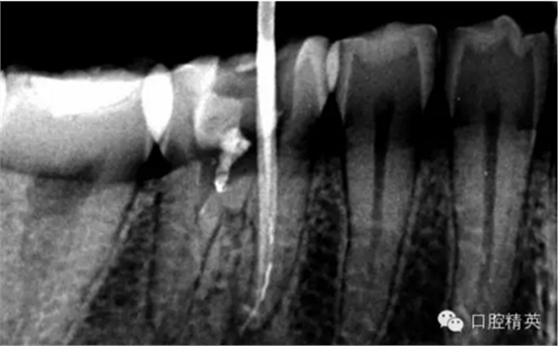

接下來第二張病例

這個也是我目前接到最有難度的器械分離病例,從片子上看近中器械分離兩節(jié),曾在外院做過干尸,有七年。當看到這個病例時我沒有多大的把握,因為我是身處基層,無顯微,無放大。我只有抱著試一試的態(tài)度,但是她是我們院內(nèi)員工,壓力很大。

現(xiàn)在開始看第二張片子我疏通的遠舌根,有點問題哦!~

根尖孔偏移,或者是片子角度問題,導致我們很難判斷,感覺像是測穿。但是我們有根測儀(前提它是好的),因為根測儀是我們目前對根管測量最具有說服力,也是最為客觀事實的。根測儀沒有顯示一探入根尖下三分之一顯示“over”的情況(我用的是登士博根測儀)根管內(nèi)無滲出,可以測出根管的長度。那就證明工作長度的存在,和可信。在看看正題的近中根的器械,我想問問大家覺得是什么器械??

近中舌根疏通,兩根分離的器械都在近中舌根。花費2個多小時。將它疏通下去還是離不開較長的時間,也就是耐心,它真的很重要哦!~第二個我覺得器械分離的疏通,就是在于能否建立旁路,那么怎么去建立這條路。我個人覺得首先挫的選擇,是k挫,是c+,還是別的什么。我的首選是8號c+,因為它夠硬,8號的k挫太軟,沒有辦法擴下去,很容易碰到根內(nèi)部器械導致器械報廢,尖端變光亮。但是c+挫也不是那么完美,我擴的時候用了4根8號新的c+挫,全部報廢。尖端彎曲90度的,有變成麻花的。這些都在提醒我可能用力過大,或者根管內(nèi)部太過于復雜。疏通時只有慢慢來,一點點的下千萬不要妄想一步到位。手法還是要輕柔否則你的器械一樣也會分離進去。疏通到挎自己的器械的時候也是碰到分離的器械時,這個時候最好是上下提拉,切勿旋轉(zhuǎn)向下,你只有盡量將該部位擴開,為下一步往下疏通留有足夠的空間就好。而不是繼續(xù)向下旋轉(zhuǎn),這樣會導致器械的分離,加大你疏通的難度。

疏通其余三根30分鐘。

近中試尖,超出,這是沒有很好的把握工作長度,這是自己在預備時可能出現(xiàn)超預備的情況,所以以后機括預備一定要注意,防止超預備,否則會導致術(shù)后疼痛。